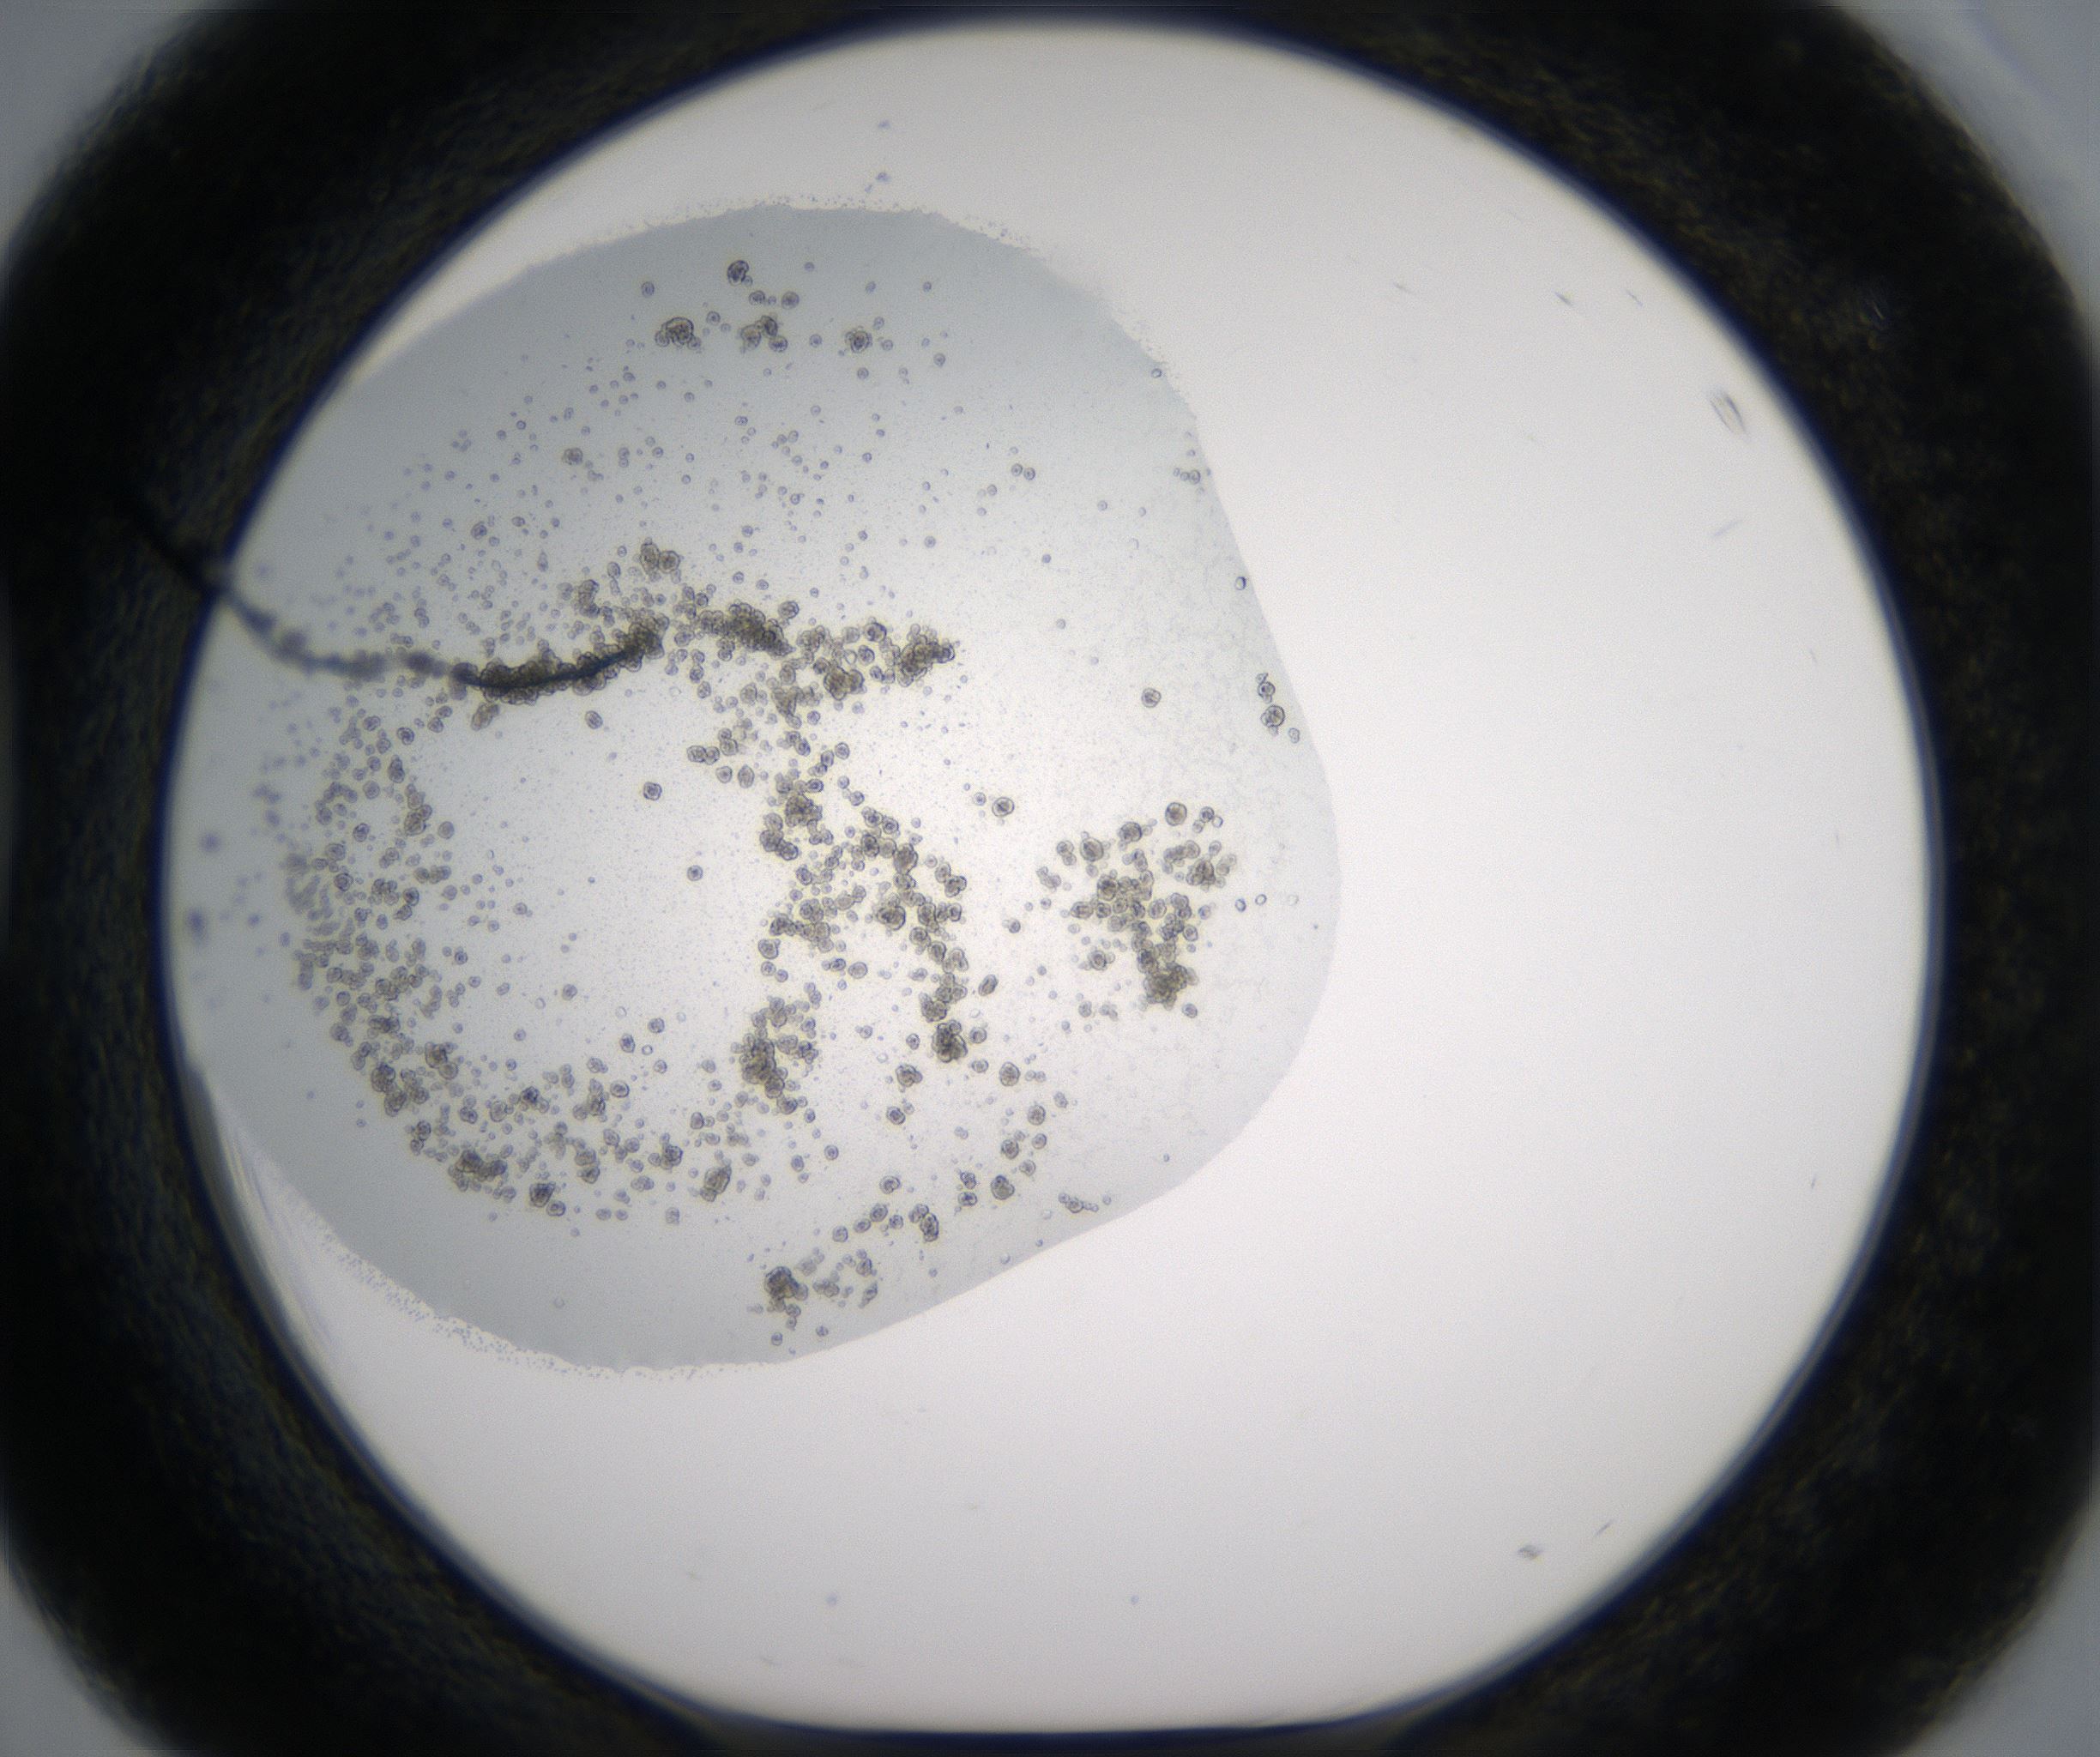

Precipitate

Organization

D3_HighResolution_Precipitate_1.jpg